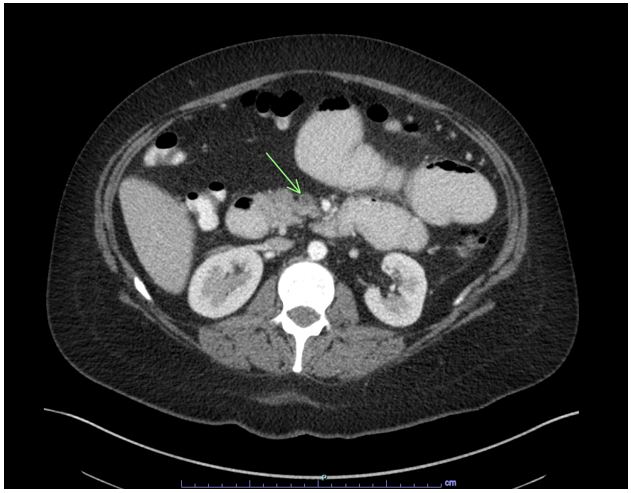

Her outside hospital CT scan was requested and upon review by our radiologists, a superior mesenteric vein thrombus was seen. A repeat CT abdomen showed dilation of the duodenum and jejunal loops proximal to the known foreign body and signs of intestinal ischemia and bowel perforation around the loop of ileum. An exploratory laparotomy that revealed small bowel perforation adjacent to the bezoar necessitating partial small bowel resection. Her symptoms improved, and she was discharged home and with follow-up for evaluation of a hypercoagulable state.

Discussion: Mesenteric venous thrombosis (MVT) is an uncommon cause of mesenteric ischemia. MVT usually involves the superior mesenteric vein (SMV) and rarely involves the inferior mesenteric or portal veins. The diagnostic modality of choice is CT angiography which reveals venous filling defects in mesenteric veins during the venous phase. The resultant venous occlusion is sufficient to produce ischemia. Our patient most likely developed the subacute form of SMV thrombosis which led to bowel wall edema and ischemia resulting in bezoar formation, small bowl obstruction, and untimely perforation.